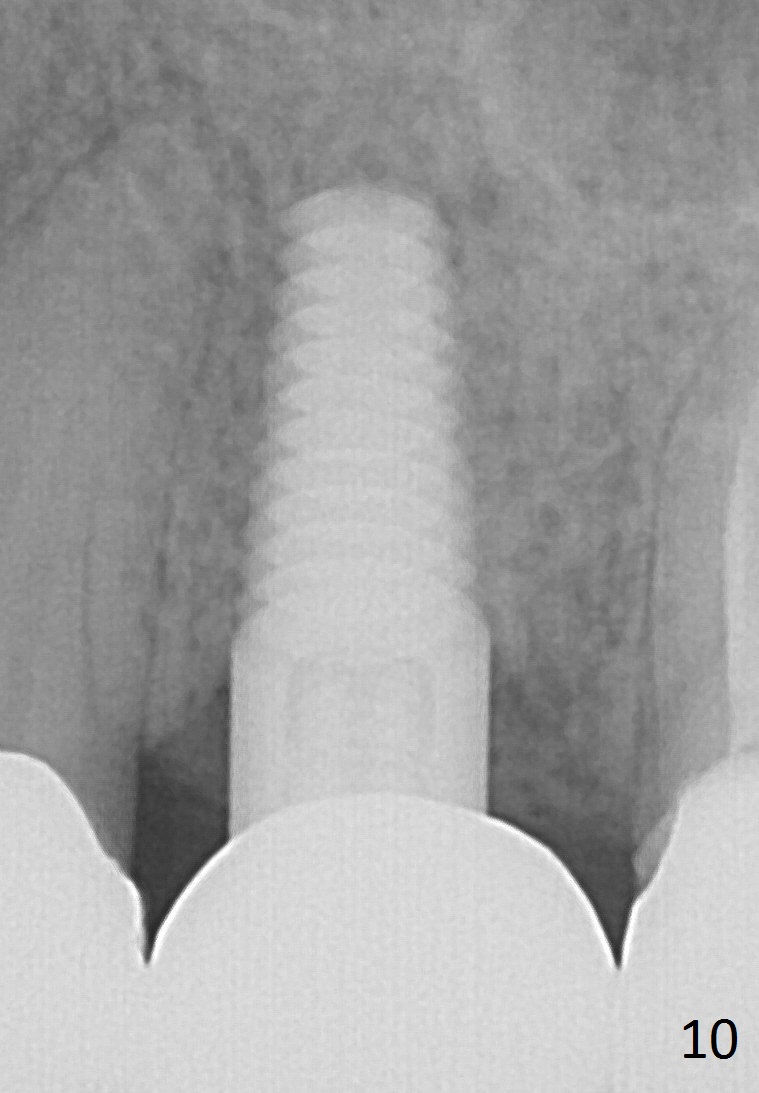

A 45-year-old lady is nervous about dental treatment. The missing tooth #13 was replaced by a 3-unit bridge. The latter is sectioned because the posterior abutment has caries. PA in Fig.1 is taken when root canal therapy and build up are finished. Fig.2 shows the wide edentulous area with a single-unit crown being tried in for #14. Osteotomy is initiated with the crown in place without cementation, since it is easy to determine the mesiodistal position (Fig.3 red lines). Without the crown in place, osteotomy tends to be distal. In this case, the osteotomy is later attempted to be moved distally with Lindamann bur and deepened to 14 mm from the gingival margin (Fig.4). A 2.5 mm reamer is being used at 50 RPM to increase osteotomy with difficulty. Drills have to used at high RPM instead (Fig.5 4x14 mm). A 4.5x14 mm tissue-level implant is placed with insertion torque >60 Ncm (Fig.6 I); a 4x3 mm abutment (A) is placed immediately for an immediate provisional. Fig.7 is taken 7 days postop to show the gingival recipient site formed by the provisional. The patient is so afraid of X-ray that the next one is taken 1.5 years post cementation (Fig.8). It appears that dense bone bundle forms between the crest and the 1st implant thread (adaptation functional change, arrowheads). The bone density continues to increase 2 years 8 months post cementation (Fig.9 *, 10); the bone has grown into the area between the 1st 2 threads (arrow).